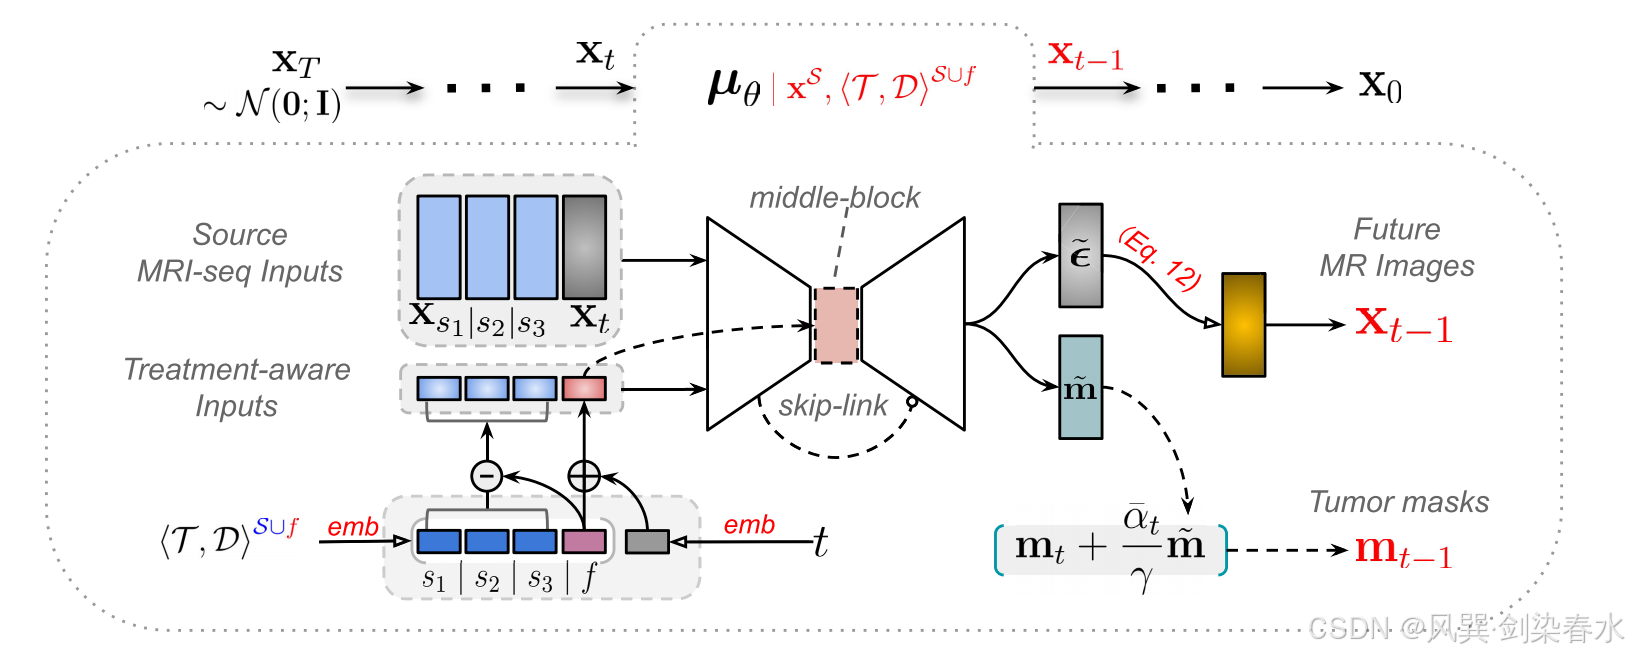

为此,本文提出了治疗感知扩散(TaDiff)模型,用于纵向数据的多参数 MRI 生成和肿瘤生长预测。 TaDiff 模型引入了一种治疗感知机制,用于在扩散模型中加入条件,同时采用联合学习策略,在扩散过程中对肿瘤进行分割并预测其未来的生长。图 2 展示了 TaDiff 流程的概览。

Figure 2 | 针对任何给定的治疗信息和目标/未来时间点,用于多参数MRI生成和肿瘤生长预测的 TaDiff 模型端到端管道:该模型以条件源 MRI 序列和治疗感知嵌入作为输入,输出目标/未来的 MRI 图像,并同时预测源治疗日点和给定的目标治疗日点的肿瘤掩模;

基于时间步嵌入的概念,本文采用两个独立的嵌入层和 MLP 层,将配对的治疗信息和日期信息(即 ⟨ τ s 1 , d s 1 ⟩ ⟨τ_{s₁},d_{s₁}⟩ ⟨τs1,ds1⟩、 ⟨ τ s 2 , d s 2 ⟩ ⟨τ_{s₂},d_{s₂}⟩ ⟨τs2,ds2⟩、 ⟨ τ s 3 , d s 3 ⟩ ⟨τ_{s₃},d_{s₃}⟩ ⟨τs3,ds3⟩ 以及 ⟨ τ f , d f ⟩ ⟨τ_f,d_f⟩ ⟨τf,df⟩)注入网络中。具体而言,四对治疗信息与天数依次输入到两个嵌入多层感知器(MLP)层中,随后将学到的治疗嵌入向量与其对应的天数嵌入向量相加,从而为每一对治疗-天数变量获得一个独特的特征向量。通过这种方式,得到了四个治疗向量:其中三个分别代表源/过去的治疗信息(用 s 1 s_1 s1, s 2 s_2 s2 和 s 3 s_3 s3 表示),另一个(用 f f f 表示)代表目标/未来的治疗信息,如 图 2 所示。

基于实验观察,本文发现采用源处理时间与目标处理时间之间的相对(差值)距离,有助于加速并稳定训练过程。因此,本文从目标向量中减去源向量,以获得其差分向量(diff-vectors),随后将这些差分向量与目标处理特征和时间步嵌入的求和向量进行拼接。

最终,使用这种新拼接的嵌入向量替代原始的时间步嵌入向量,通过 U-Net 进行前向传播,但中间块部分(如 图 2 所示)除外。在 U-Net 的中间块(亦称为 bottle-neck )中,仅注入时间步与目标处理嵌入之间求和的特征。基于实验观察,这种方法在将目标处理信息融入扩散时间步时,能够提供平稳且快速的学习过程。

在模型的输入中,将源多参数 MRI(即 x s 1 x_{s1} xs1、 x s 2 x_{s2} xs2 和 x s 3 x_{s3} xs3)与 x t x_t xt 连接。需要注意的是, x t x_t xt 是带有扩散噪声的目标 MRI。模型有两个输出:

(1)第一个输出是在时间步 t t t 处估计的扩散噪声,这可以用来生成图像;

(2)第二个输出是从源 MRI( x S x^S xS)和带噪声的目标 MRI ( x t x_t xt)预测出的肿瘤掩模;

因此,TaDiff 模型不仅仅是一个纯粹的扩散模型,而是一个结合了去噪扩散和分割任务的混合网络,能够以端到端的方式生成未来的 MRI 图像并同时分割出肿瘤的纵向生长掩模。算法1 和 算法2 介绍了 DDPM 训练和采样过程。

需要注意的是,扩散分支和分割分支共享编码器组件。扩散过程需要 600 步来生成目标图像,而分割过程仅利用最后 10 步。这些最后的步骤提供了质量最高的输入,本文生成 10 个 mask。随后对这些 mask 进行加权平均,以生成最终的分割 mask。这种方法确保分割 mask 能够从扩散过程后期阶段产生的高质量输入中获益。